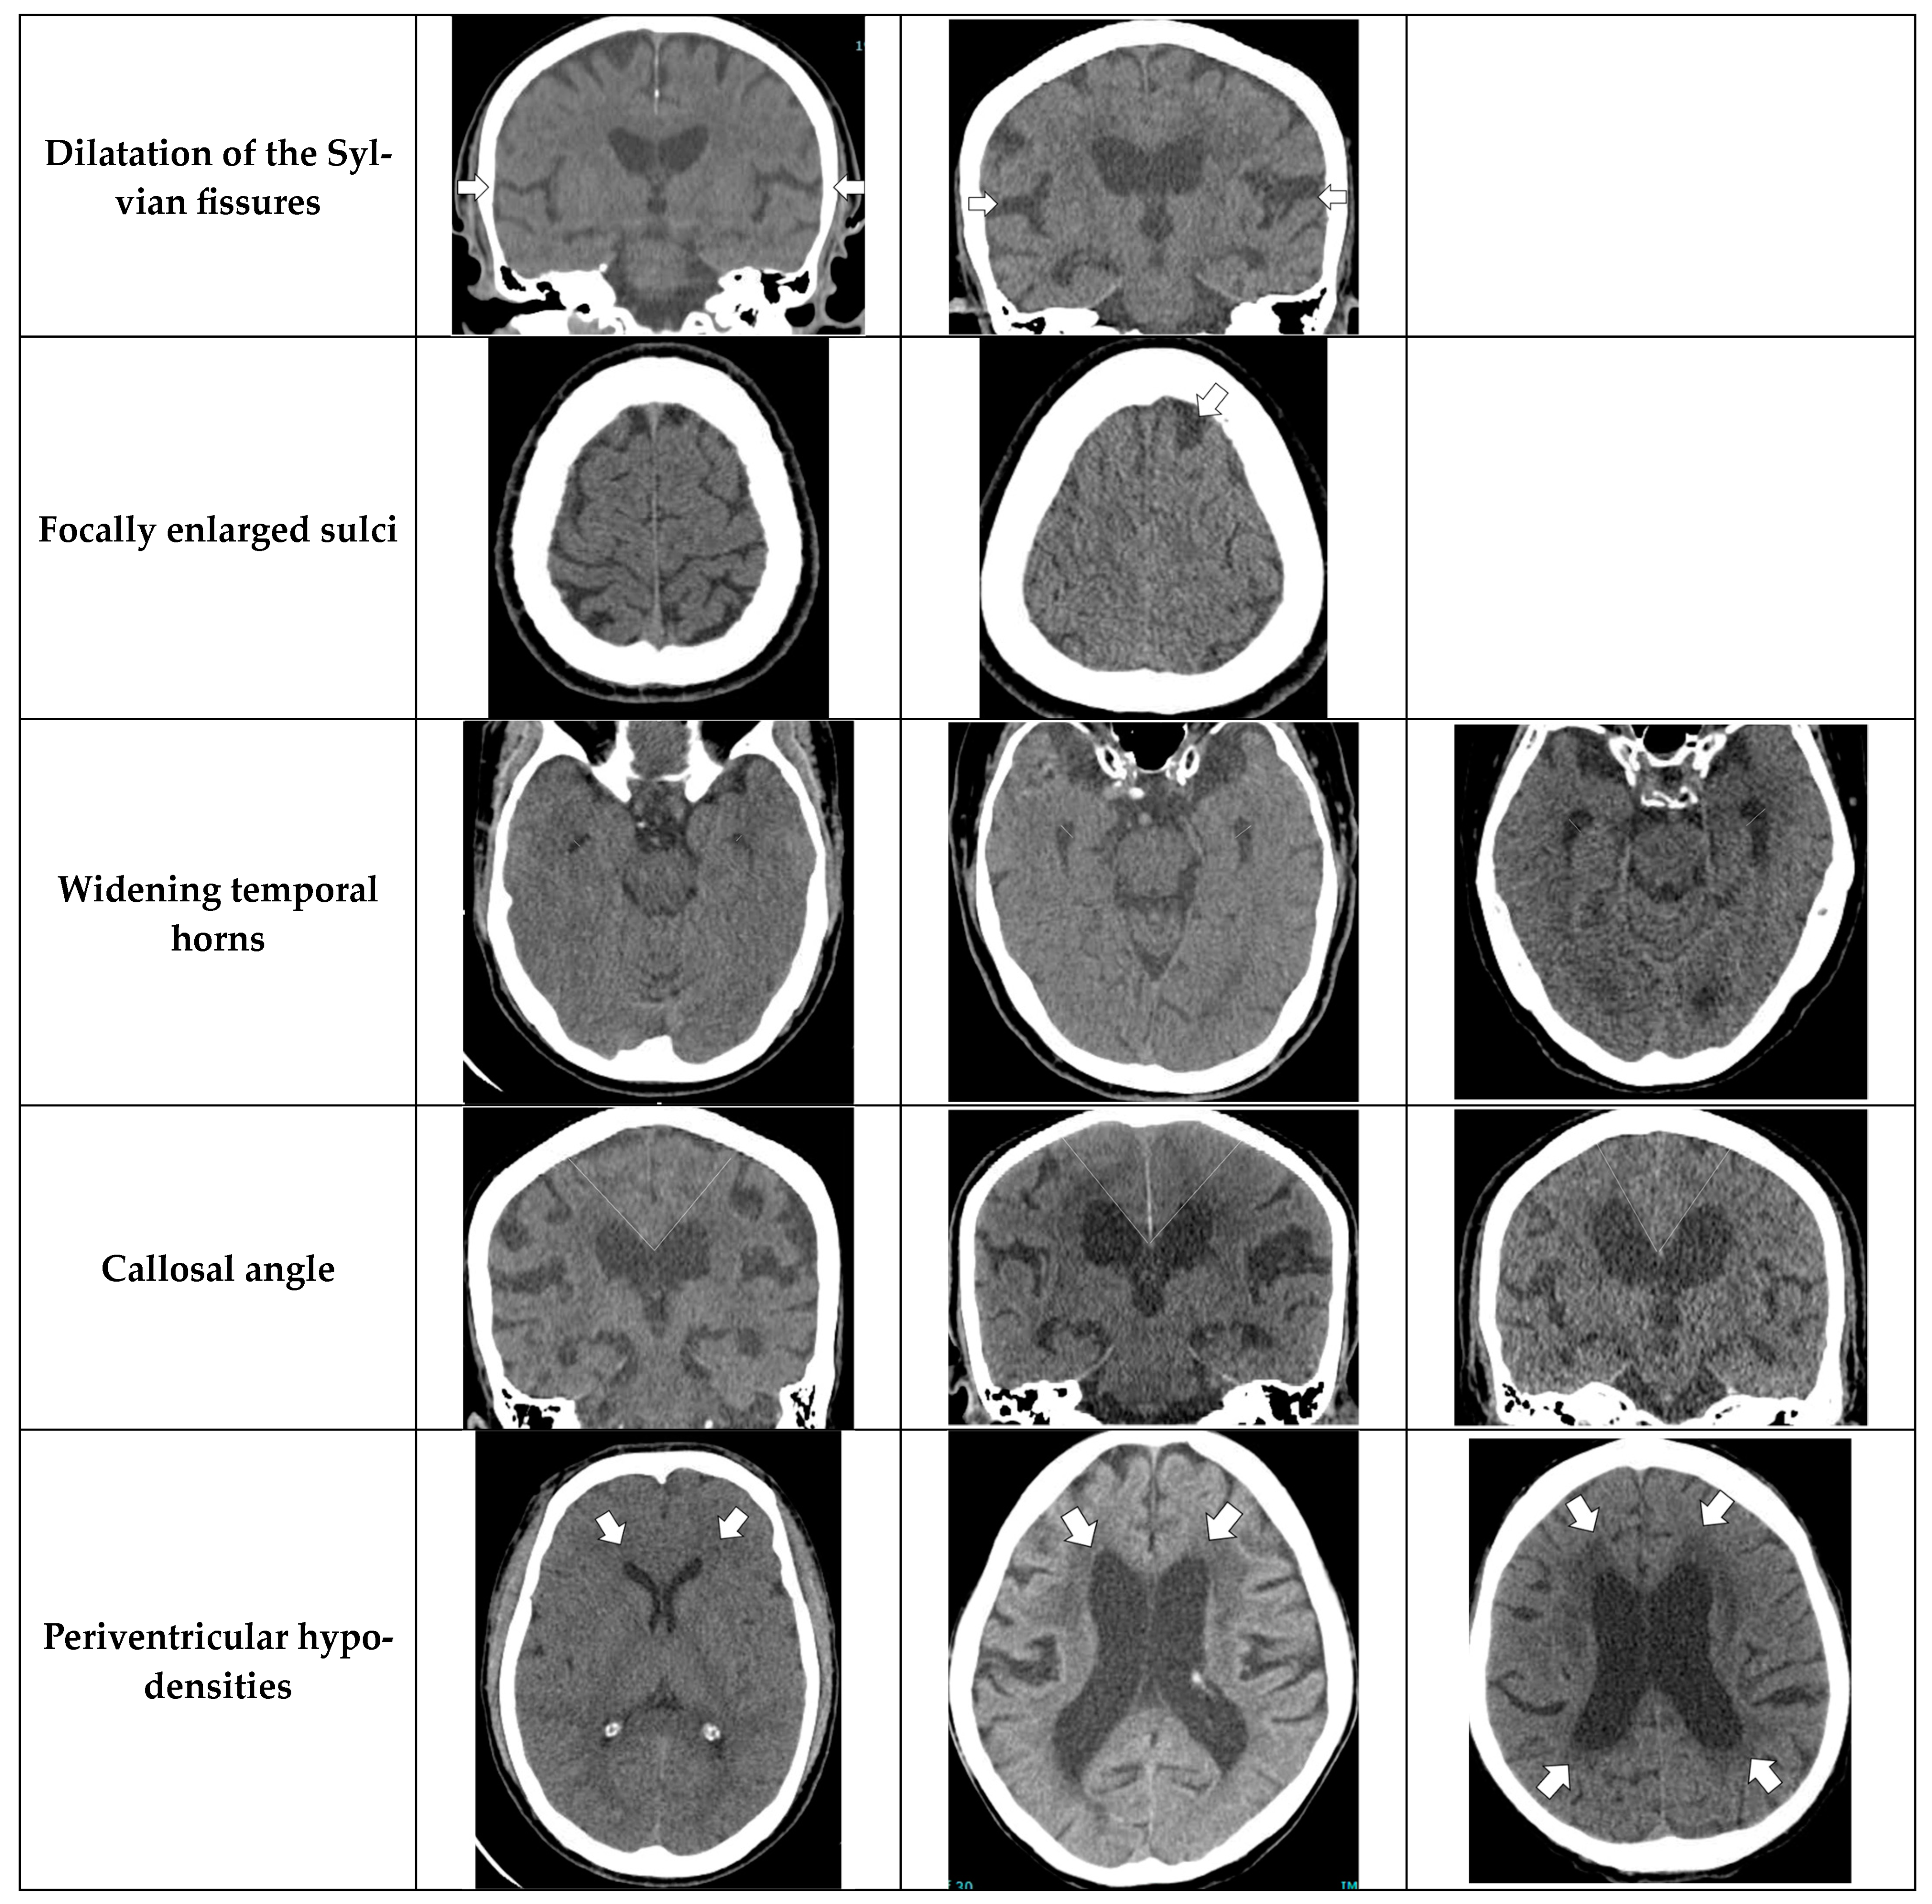

- Evans’ index: The ratio between the maximal width of the frontal horns of the lateral ventricles (B–C) by the maximal width of the inner table of the cranium in the same axial image [9].

- Narrow parietal sulci: At high-convexity and parafalcine region assessed in both axial planes in the most superior slices and coronal plane [10].

- Dilation of the Sylvian fissures: Reported as present or not present in the coronal plane compared with surrounding sulci [11].

- Focally enlarged sulci: Compared with surrounding sulci, usually found in coronal or axial planes [12].

- Temporal horns: Reported as mean width of the right and left side, measuring in the axial plane [11].

- Callosal angle: Angle between the lateral ventricles in the coronal plane through the posterior commissure perpendicular to the intercommissural plane [13].

- Periventricular hypodensities: Along the lateral ventricles graded as not present, present as a cap around frontal horns or confluently extending around the lateral ventricles [14].